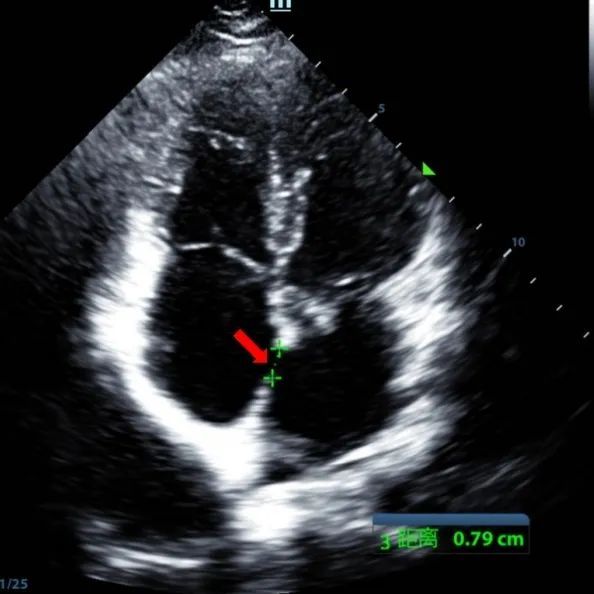

Se trató a un varón de 9 años de edad con ASD secundario (7,5-7,9mm) usando un oclusor de 12mm BDASD-I MemoSorb y un sistema de administración de 12F. No se observaron complicaciones ni comorbilidades antes del procedimiento.

Serial echocardiographic follow-ups showed stable device position and favorable cardiac remodeling. Gradual degradation confirmed the occluder's long-term safety and efficacy.